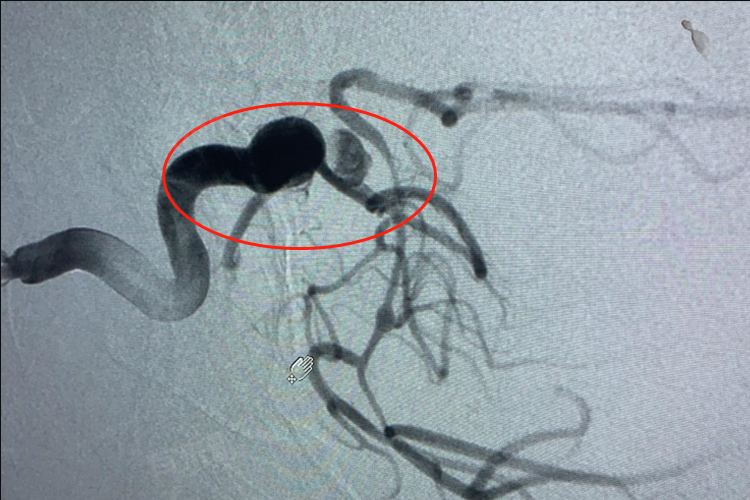

- 颈内动脉C6段动脉瘤是指发生在颈内动脉海绵窦段的动脉瘤,动脉瘤本身并非肿瘤,而是动脉壁局部的薄弱和膨出,其严重程度取决于动脉瘤的大小、形态、位置、生长速度以及是否破裂等因素。

- 随着动脉瘤的增大或形态变得不规则,其破裂的风险也会相应增加,一旦动脉瘤破裂,会导致严重的颅内出血,是一种极其危急的情况,可能引起剧烈头痛、呕吐、意识障碍,甚至危及生命。

- 动脉瘤的位置也会影响其严重程度,如果动脉瘤靠近重要的神经结构,如动眼神经、滑车神经等,即使动脉瘤未破裂,也可能由于对周围神经的压迫而导致相应的神经功能障碍,如眼睑下垂、眼球运动障碍等。